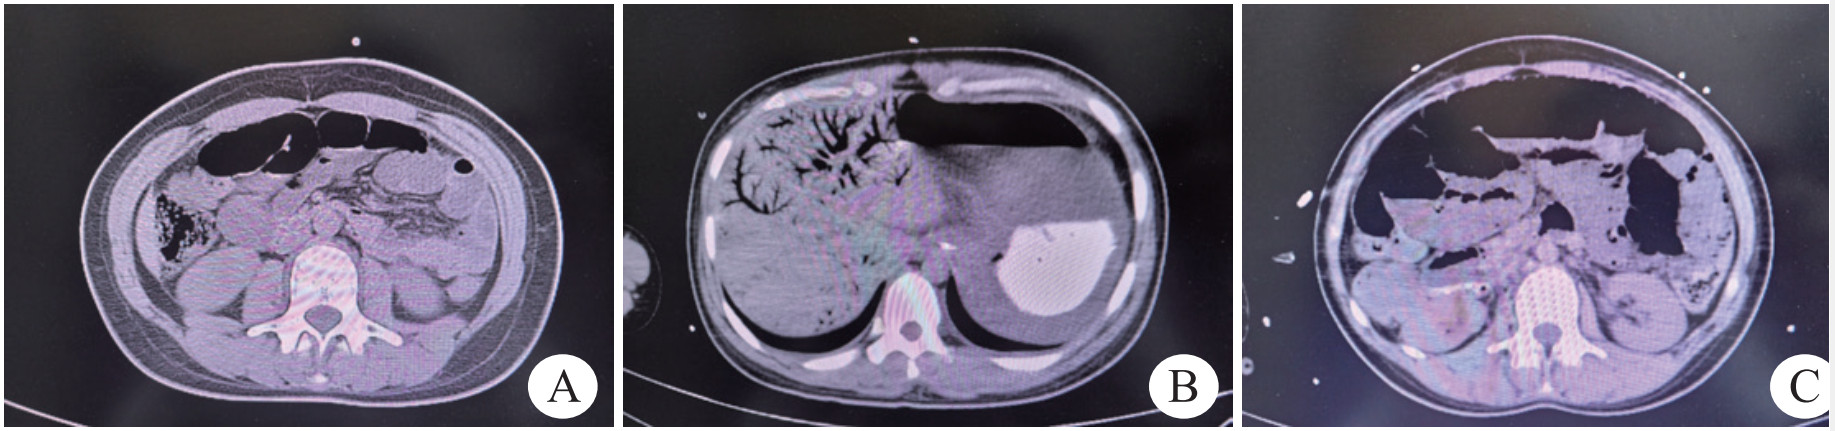

患者,女性,21岁,因“自服150 mL敌草快(diquation, DQ)3 h”于2024年5月9日02:37入院。既往抑郁症病史。入院3 h前患者自服DQ 150 mL后出现胸痛、腹痛伴恶心、呕吐,无意识障碍、抽搐,无发热、呼吸困难、腹泻等,就诊于当地医院,给予洗胃处理后转至本院。入院查体:体温36 ℃,心率120次/min,呼吸43次/min,血压166/98 mmHg(1 mmHg=0.133 kPa),血氧饱和度98%,神志清楚,痛苦面容,口腔黏膜未见异常,听诊双肺呼吸音清,无干、湿啰音。心律齐,各瓣膜听诊区未闻及病理性杂音。腹部平坦,肠鸣音3次/min,软,上腹部压痛,无反跳痛。双下肢无浮肿。辅助检查:动脉血气分析:pH 7.48,氧分压88 mmHg,二氧化碳分压22 mmHg,乳酸4.2 mmol/L; 血常规:白细胞计数17.1×109/L,中性粒细胞百分比83.1%,血红蛋白、血小板计数正常; 肝肾功能、电解质、凝血功能、心肌损伤标志物、B型钠尿肽、降钙素原正常。次日03:00时毒物分析示血液DQ浓度16 500 ng/mL,尿液DQ浓度:1 947 000 ng/mL。头、胸部CT未见明显异常。腹部CT:小肠管多发液平面,未见肠管扩张(如图 1A)。入科后给予20%甘露醇250 mL导泄,蒙脱石散30 g吸附,并行血液灌流1次,同时给予维生素C、谷胱甘肽抗氧化治疗。08:45时复查毒物分析示血液DQ浓度6 870 ng/mL。但患者病情未见好转,随后出现烦躁不安、血压下降、无尿以及严重代谢性酸中毒,在与家属沟通后,给予患者气管插管接呼吸机辅助呼吸,给予镇痛镇静、去甲肾上腺素升压治疗,并行持续床旁血液透析滤过联合血液灌流治疗。20:33时发现患者腹部膨隆,听诊肠鸣音消失,复查腹部CT:肝脏门静脉(如图 1B)、肠壁内多发积气,腹盆腔多发肠道扩张伴液平,考虑肠梗阻(如图 1C); 胃壁水肿并胃周积液; 盆腔少量积液。测腹内压23 cmH2O(1 cmH2O=0.098 kPa),诊断为麻痹性肠梗阻,肝门静脉积气(hepatic portal venous gas, HPVG),腹腔间隔室综合征,请胃肠外科会诊,考虑患者目前状态不适宜手术,给予胃肠减压,肛管排气治疗,给予亚胺培南西司他丁钠1 g间隔6 h静脉滴注,但患者病情继续恶化,次日复查血生化:丙氨酸氨基转移酶901 U/L,天门冬氨酸氨基转移酶521 U/L,肌酐109 µmol/L,血常规:白细胞计数7.14×109/L,超敏C反应蛋白72.9 mg/L,降钙素原:85.48 ng/mL,血培养阴性。最终于5月10日14:30抢救无效死亡。

| 注:A为小肠管多发液平面,未见肠管扩张; B为肝脏门静脉积气; C为肠壁内多发积气,腹盆腔多发肠道扩张伴液平 图 1 患者入院及18 h时腹部CT变化 |

本例患者口服了150 mL DQ后迅速出现了肝肾、呼吸、循环等多器官、多系统功能衰竭,并且导致了严重的麻痹性肠梗阻,以及临床罕见的HPVG。HPVG不是一个独立的疾病,而是指由各种原因引起的门静脉及肝内门静脉分支中气体异常积聚的影像学征象,其起病急,病情变化快,预后差,病死率极高,又被称为“死神之征”[2]。目前关于HPVG的原因有三种假设[3],①感染:产气荚膜梭菌、大肠杆菌、肺炎克雷伯菌等产气细菌侵入肠壁或门静脉繁殖产生气体; ②肠黏膜损伤、肠腔压力升高; 肠内气体在肠黏膜损伤的情况下,可在肠腔压力升高的作用下通过受损的黏膜进入门静脉系统; ③混合型:感染与黏膜损伤相互作用的结果。结合该例患者,分析其发生HPVG的原因可能是混合型因素。一方面,DQ直接腐蚀肠黏膜,造成肠黏膜屏障受损,同时,DQ引起了麻痹性肠梗阻,肠道压力明显升高,气体通过受损黏膜进入门静脉系统。另一方面,患者复查降钙素原显著升高,CT见肠壁内多发积气,考虑不除外肠道细菌移位,产气菌侵入肠壁或门静脉繁殖产生气体。

最后,本例患者入院时即进行了腹部CT检查,虽当时就见小肠管多发液平面,但未见肠管扩张,因此未考虑肠梗阻,考虑其不除外与洗胃有关。因此根据2020年急性敌草快中毒诊断与治疗专家共识[1],给予了蒙脱石30 g吸附治疗,但随后患者出现了严重麻痹性肠梗阻及HPVG。虽然其主要原因仍考虑与DQ中毒有关,但是大剂量蒙脱石是否导致了肠梗阻加重,出现HPVG,以及如何在临床中避免这一问题发生还需进一步探讨。